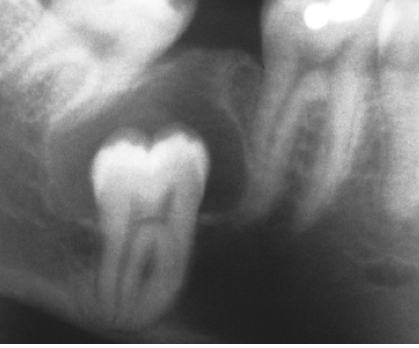

What is the likely Dx?

Dentigerous cyst.